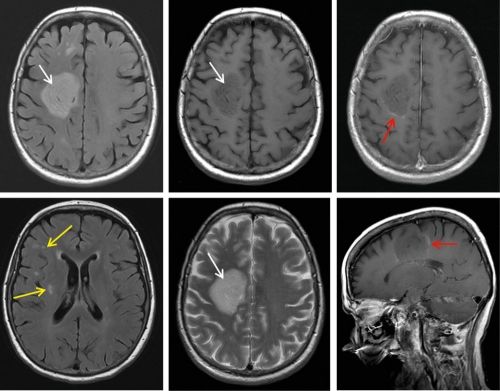

Эта болезнь носит хронический характер и поражает головной и спинной мозг. К сожалению, заболевание неизлечимое и возникает оно из-за воспалительных очагов в миелиновой оболочке, защищающей нервные волокна мозга и позвоночника. На 100 тыс. человек приходится 30-70 случаев рассеянного склероза – достаточно распространенная болезнь.